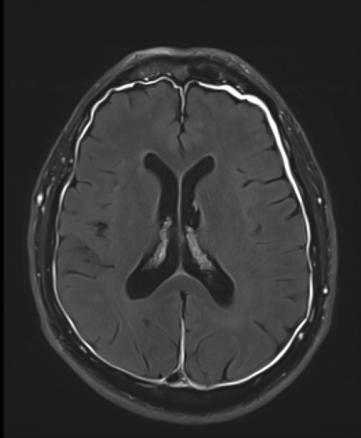

Pachyméningite sustentorielle

Épaississement de la méninge.